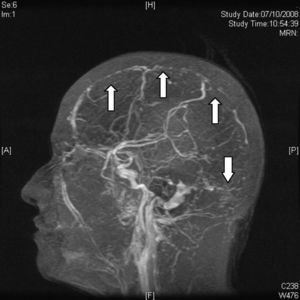

AnatomíaEl drenaje venoso del cerebro se realiza por un sistema venoso superficial y otro profundo que drena hacia los principales senos durales: seno sagital superior (SSS), seno sagital inferior (SSI), senos laterales (SL), seno cavernoso y seno recto (fig. 1). El drenaje final se realiza a través de la vena yugular interna. Las venas del sistema venoso superficial, que drenan principalmente al SSS y a los SL, cuentan con numerosas anastomosis y en casos de oclusión son de difícil diagnóstico. El sistema venoso profundo drena sangre desde la sustancia blanca profunda de los hemisferios y los ganglios basales en la vena de Galeno. Tanto el sistema venoso superficial como el profundo tienen múltiples anastomosis. Lo anterior permite que el drenaje venoso tome vías alternas de acuerdo con diferentes necesidades, como en el caso de una trombosis4,5.

Anatomía normal de los principales senos venosos en imagen por resonancia magnética en fase venosa. CS: confluencia de los senos (presa de Herófilo); VAI: vena anastomótica inferior (de Labbé); VAS: vena anastomótica superior (de Trolard); VB: vena basal (de Rosenthal); VCI: vena cerebral interna (de Galeno); VCS: venas cerebrales superficiales; SR: seno recto;SS: seno sigmoideo; SSI: seno sagital inferior; SSS: seno sagital superior; ST: seno transverso o lateral.

Resonancia magnéticaEn la actualidad el diagnóstico de TVC se confirma con IRM combinada con venorresonancia. La IRM tiene una sensibilidad más elevada para detectar las alteraciones del parénquima cerebral, formación de trombos, hemorragias petequiales y flujo sanguíneo31. El protocolo de estudio incluye secuencias T1 (con y sin contraste), T2, FLAIR, difusión y venografía27 (fig. 4). De acuerdo a la evolución de la TVC el coágulo puede tomar diferentes aspectos, por ejemplo, en etapas muy tempranas o agudas (< 5 días), los vasos ocluidos aparecen isointensos en secuencias en eco de espín ponderadas en T1 e hipointensos en T2. A partir del día 5 y hasta el día 35 la oxihemoglobina del trombo se convierte gradualmente en metahemoglobina y podemos observar imágenes hiperintensas en T1 y en T232. En etapas tardías o crónicas el patrón de presentación en IRM es más variable. El seno venoso trombosado puede recanalizarse o permanecer ocluido de forma parcial o completa, lo que puede ser interpretado como TVC recurrente. Por lo anterior, la venorresonancia (fig. 5) y la TC helicoidal están indicadas en las etapas tempranas menores a 5 días y en las etapas tardías (> 6 semanas), períodos en los que la IRM puede mostrar falsos negativos. A los 6 meses las anormalidades en los estudios de imagen persisten en aproximadamente dos tercios de los pacientes. Los falsos positivos se deben a un flujo sanguíneo venoso lento sin trombosis. Las secuencias de venorresonancia incluyen: TOF (time of flight) y contraste de fase. Las de contraste de fase son de adquisición rápida y permiten analizar tanto la dirección del flujo como su cuantificación en la vasculatura obstruida33.